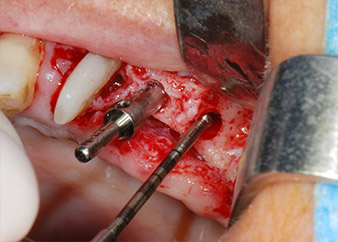

En primer lugar, en un intento por gestionar el problema endo-periodontal, el resto de la superficie radicular se desbridó con cuidado con un equipo piezoeléctrico (Piezomed de W&H, utilizado con el inserto S1 con forma de espátula, concebido en un principio para la erosión de la pared lateral del seno) (figura 4). A continuación, el ápice se erosionó con el mismo instrumento para eliminar el tejido apical infectado residual y reducir las posibles ramificaciones accesorias del canal radicular (apicectomía) (figura 5). No fue necesario realizar un retrorellleno, puesto que la obturación ortógrada se acababa de revisar.

Antes de colocar el implante, el tejido infectado del hueso alveolar ubicado en el lugar del implante y alrededor de los dientes del pilar se retiró con un inserto concebido en un principio para modelar huesos y recoger virutas óseas: Piezomed y el inserto B5 (figuras 6 y 7).